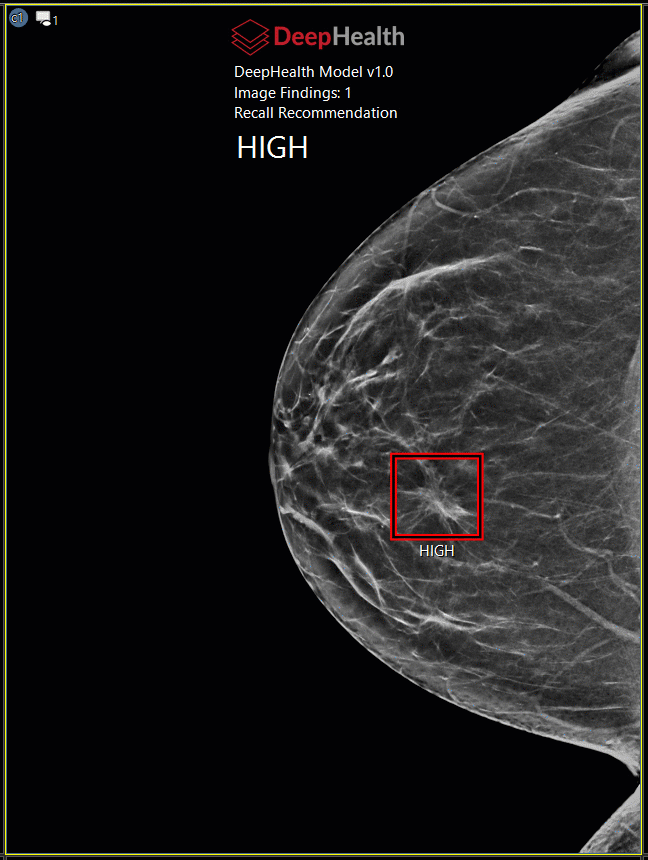

A CAD mutató számítógéppel támogatott diagnózist nyújt a mammográfia képekhez.

DeepHealth, Inc. |

Saige |

(2.1.0) |

7.2, 8.0 (Evo) |

CAD overlayek

Ha a vizsgálat CAD mutatót tartalmaz, a prezentációs állapot ikon (kiemelve) megjelenik a kép bal felső sarkában, ha az egy képkockában jelenik meg.

Egyes CAD-gyártók esetpontszámokat és/vagy leleteket adnak. Az eset pontszáma a CAD fejlécben található, és a képen lévő jelölés mellett egy egyedi leletpontszám látható.